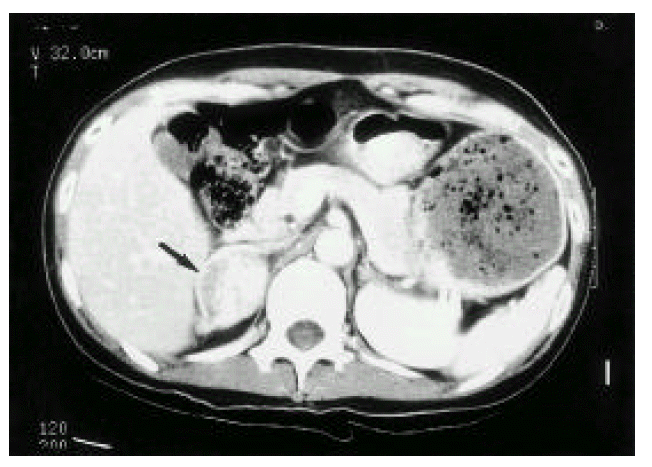

Fig. 3.

Abdominal CT showing a well enhanced oval-shaped adrenal mass (arrow).

A 34-year-old pregnant woman underwent a normal vaginal delivery. She had no previous history of hypertension and there was no evidence of toxemia in pregnancy or preeclampsia in the prenatal examination. At the terminal period of pregnancy, the patient showed mild hypertension, which was well controlled by nifedipine. Immediately after delivery, her blood pressure rose rapidly and showed marked fluctuation (140/90~210/90 mmHg). The pulse rate increased from 70/min to 150/min. The patient complained of a severe headache, palpitations, chest discomfort, dyspnea and postural dizziness. The blood pressure and pulse rate could not be controlled by nifedipine and her symptoms worsened. Her breathing sounds were normal and the heart sound was regular; there was no murmur. The abdominal mass was not palpated. No periumbilical bruit was heard. Blood tests and simple chest X-ray showed no abnormal findings. Serum CK/CK-MB/LDH levels were 268/23/607 U/L. There was no interval change in serum CK/CK-MB/LDH levels in serial follow-up. The electrocardiograph showed sinus tachycardia, left ventricular hypertrophy and a non-specific ST change in the precordial leads (Fig. 1). In the transthoracic echocardiograph, left ventricular contraction was depressed (ejection fraction = 25%) and akinesia of the septal, anterior and inferior walls was noted (Fig. 2). In a 24-hour urine collection, the total metanephrine level was 15.4 mg/day (normal value; 0~1.2 mg/day), the vanilmandelic acid (VMA) level was 26.6 mg/day (normal value; 2.0~10 mg/day), the epinephrine level was 1682 ug/day (normal value; 0~40 ug/day) and the norepinephrine was 3111 ug/day (normal value; 0~80 ug/day). The serum norepinephrine and epinephrine levels were 4791 pg/ml (normal value; 100~410 pg/ml) and 1657 pg/ml (normal value; ä120 pg/ml), respectively. The abdominal computerized tomography (CT) showed a well-enhanced oval-shaped mass in the right adrenal gland (4.5cm × 3.6cm) (Fig. 3). The patient was diagnosed with pheochromocytoma on the 2 day after delivery. Cardiomyopathy induced by increased catecholamine was also diagnosed because of the abnormal echocardiographic findings.